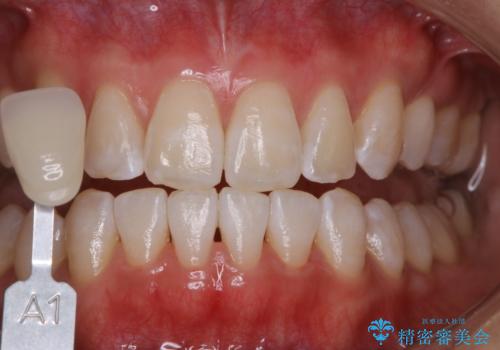

- 歯科がかなり久しぶりで、今後虫歯治療予定のためまずはクリーニングを希望されました。PMTC60分コースを行いました。

歯の表面に、茶色く色が残っている所がありますが、これは詰め物の変色の所と、虫歯になっている所です。以前に、CR(コンポジットレジン)による虫歯治療がされています。

CRは経年的劣化や、着色してしまうことがあります。PMTCでクリーニングを行うと、古いCRが目立つことがあるため、気になる際は詰め替えを行います。

茶色くなっている部分が、着色なのか、劣化なのか、虫歯によるものなのかは判別が難しいことがあります。そのため、定期的にPMTCを行うことで状態の確認が的確に行えます。

また、治療が開始される前などにも、全体的にクリーニングを行いご自身本来の歯の色、状態を精密に確認することが大切です。